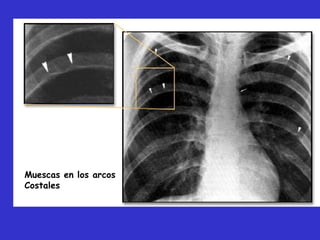

esofagrama, 3 invertido. Muescas en los

arcos costales.

Muescas en los arcos

Costales

Muescas en losarcos Costales